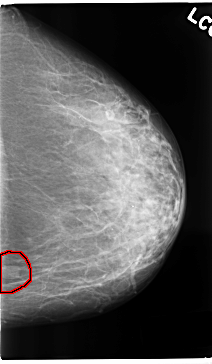

C_0259_1.LEFT_CC

LEFT_CC LINES 4728 PIXELS_PER_LINE 2744 BITS_PER_PIXEL 12 RESOLUTION 50 OVERLAY

FILE: C_0259_1.LEFT_CC.OVERLAY

TOTAL_ABNORMALITIES 1

ABNORMALITY 1

LESION_TYPE MASS SHAPE OVAL MARGINS CIRCUMSCRIBED

ASSESSMENT 4

SUBTLETY 5

PATHOLOGY BENIGN

TOTAL_OUTLINES 1

BOUNDARY